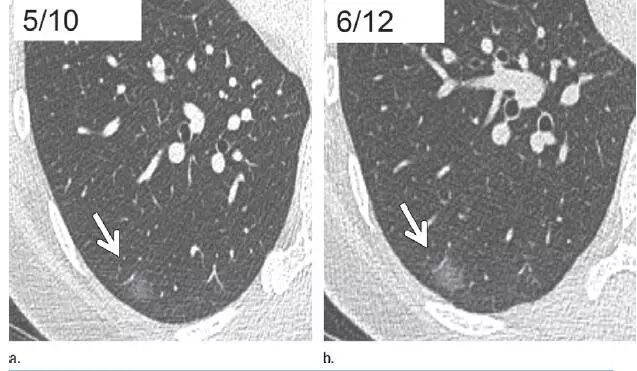

7. 相隔10个月的囊肿渐进表现

图 7 相隔 10 个月后进行的层厚 1 mm CT 横断面图像,显示右肺下叶囊肿壁渐进增厚的高度可疑模式(箭头)。手术证实为浸润性腺癌。